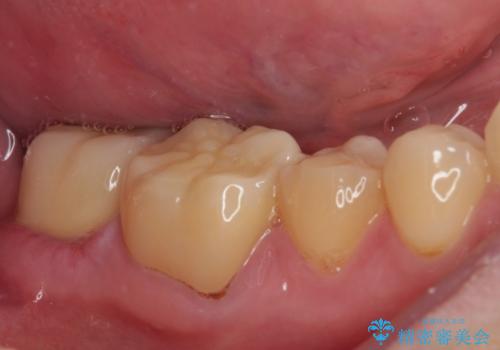

- 東南アジアへの長期赴任を前に、以前から気になっていたむし歯を治療したいとのことで来院された患者様です。

レントゲン写真から、神経の近くにまでむし歯が及んでいる様子が分かり、範囲も広範囲であったので、まずは仮歯に置き換え、その後オールセラミッククラウンにて補綴治療を行うこととしました。

処置を開始するに当たり検査診断を行ったところ、歯髄組織にまでむし歯が及んでいる可能性が示唆されたため、万が一の事態に備えてラバーダム装着による無菌的環境にて虫歯除去を行うこととしました。